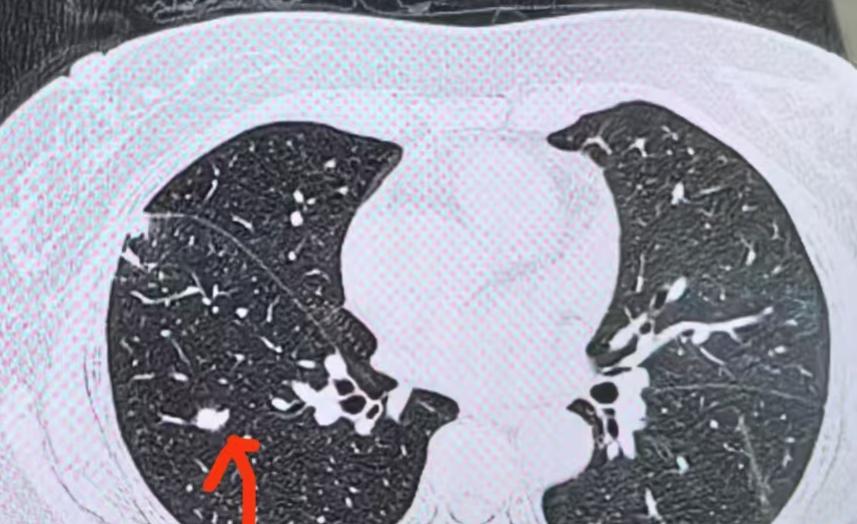

门诊印象最深的是,是有几位得过肿瘤的朋友,又发现了肺结节。第一反应往往是:这些结节是不是转移?比如今天我遇到的病例,就涉及肠癌、子宫肉瘤、肝脏肿瘤,还有咽喉部肿瘤。 肺部其实是全身肿瘤“最容易”转移的部位!这是因为肺部的血管非常丰富,而且人体的所有血流都会经过肺部。 一旦肿瘤细胞进入血液系统,就容易在肺内“停留”下来,进而繁殖、形成结节,也就是转移瘤。 所以,只要曾经患过肿瘤,又在肺里发现结节,就一定要提高警惕。 那么,如何判断这些肺结节是不是转移瘤? 主要靠影像学检查。转移瘤在影像上通常表现为小而圆的形状,边缘光滑,密度均匀,而且多数位于肺的外周。 这是因为人体的血管越到外周越细,血流中的肿瘤细胞更容易在这些细小的末梢血管中停留。 因此,典型的转移瘤影像特征就是位于肺外周、边缘光滑、密度均匀的小结节,并且常常是多发的。 当然,最准确的判断方法还是“病理活检”。 如果确诊为转移瘤,应该如何治疗呢? 1、必须进行全身系统治疗,也就是药物治疗。因为肿瘤细胞已经进入血液,用药控制全身病情是最关键的。 2、要重视局部治疗。比如我今天看到一位患者,是从肠癌转移到肺部,但全身其他地方都没有转移,肺内的转移瘤数量有限,经过观察也只是慢慢长大,并没有新增。 对于这种情况,就可以通过手术、消融等局部治疗手段,取得很好的效果。 已有不少研究证实,如果转移瘤仅局限于肺部,全身其他部位没有转移,而且肺内转移瘤数量清晰可数,不是弥漫性分布,那么通过综合治疗以及手术、消融等局部干预,完全可以获得良好的治疗效果,甚至实现长期生存。[作揖][玫瑰]